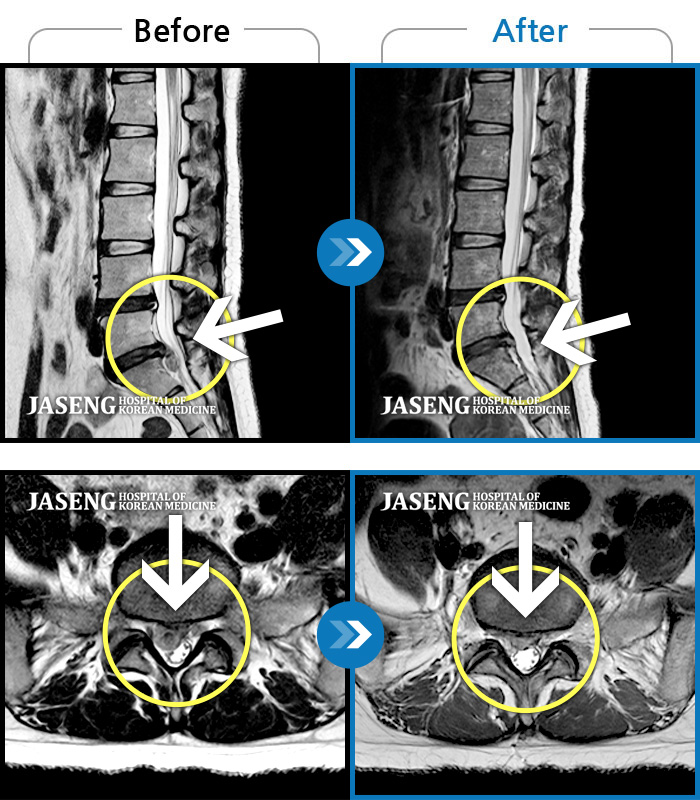

허리디스크

보라매 · 신원준 원장

좌측 허리부터 고관절 통증이 심하고 다리까지 저려서 허리를 똑바로 펴기 힘들어요.

촬영시기

2023.08.21 ~ 2023.11.20

2023.12.08